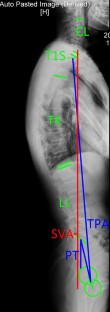

This cross-sectional, prospective study included a total of 235 volunteers aged 19 to 71 years. Volunteers were divided into two groups: group A (age ≤ 40 years; n = 140) and group B (age > 40 years, n = 95). Student’s t test was performed to compare the sagittal parameters including sagittal vertical axis (SVA), T1 pelvic angle (TPA), cervical lordosis (CL), thoracic kyphosis (TK), lumbar lordosis (LL) and pelvic tilt (PT) between standing and sitting positions of two groups. Multiple regression was performed to explore the influence factors of differences between two positions.

Fig. 1